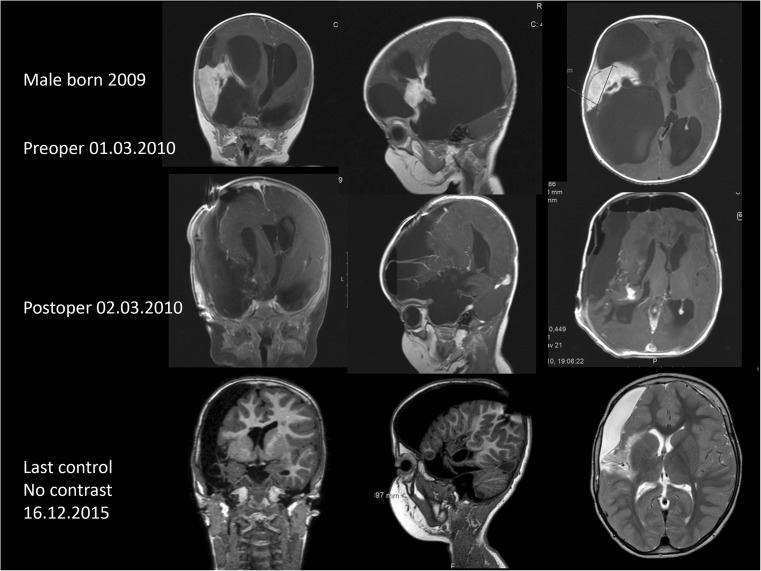

Fig. 1.

Pre- and postoperative as well as follow-up MRIs in patient 19